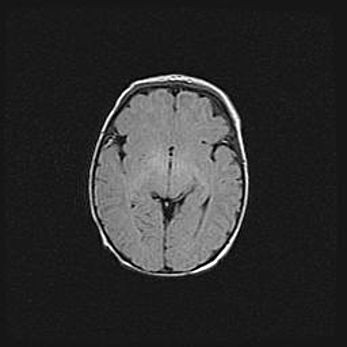

Неполная лизэнцефалия (пахигирия). Открытая гидроцефалия.

Возраст: 17 дней

Вес: 3110 г

Пол: мужской

Окружность головы: 33,5 см

Срок гестации: 35-36 недель

Лизэнцефалия—недоразвитие корковой пластинки и мозговых извилин в результате нарушения миграции нейронов коры. Поверхность мозговых полушарий гладкая. Микроскопически выявляется отсутствие нормальных слоев коры и скопление групп нейронов в подкорковом белом веществе.

Пахигирия—уменьшение числа вторичных извилин. В пораженном полушарии нервные клетки образуют толстый недифференцированный слой с неправильно расположенными нервными волокнами и группами гетеротопных клеток. Нервные клетки незрелые. Белое вещество истончено. При этом нередко аномально развит корково-спинномозговой путь.